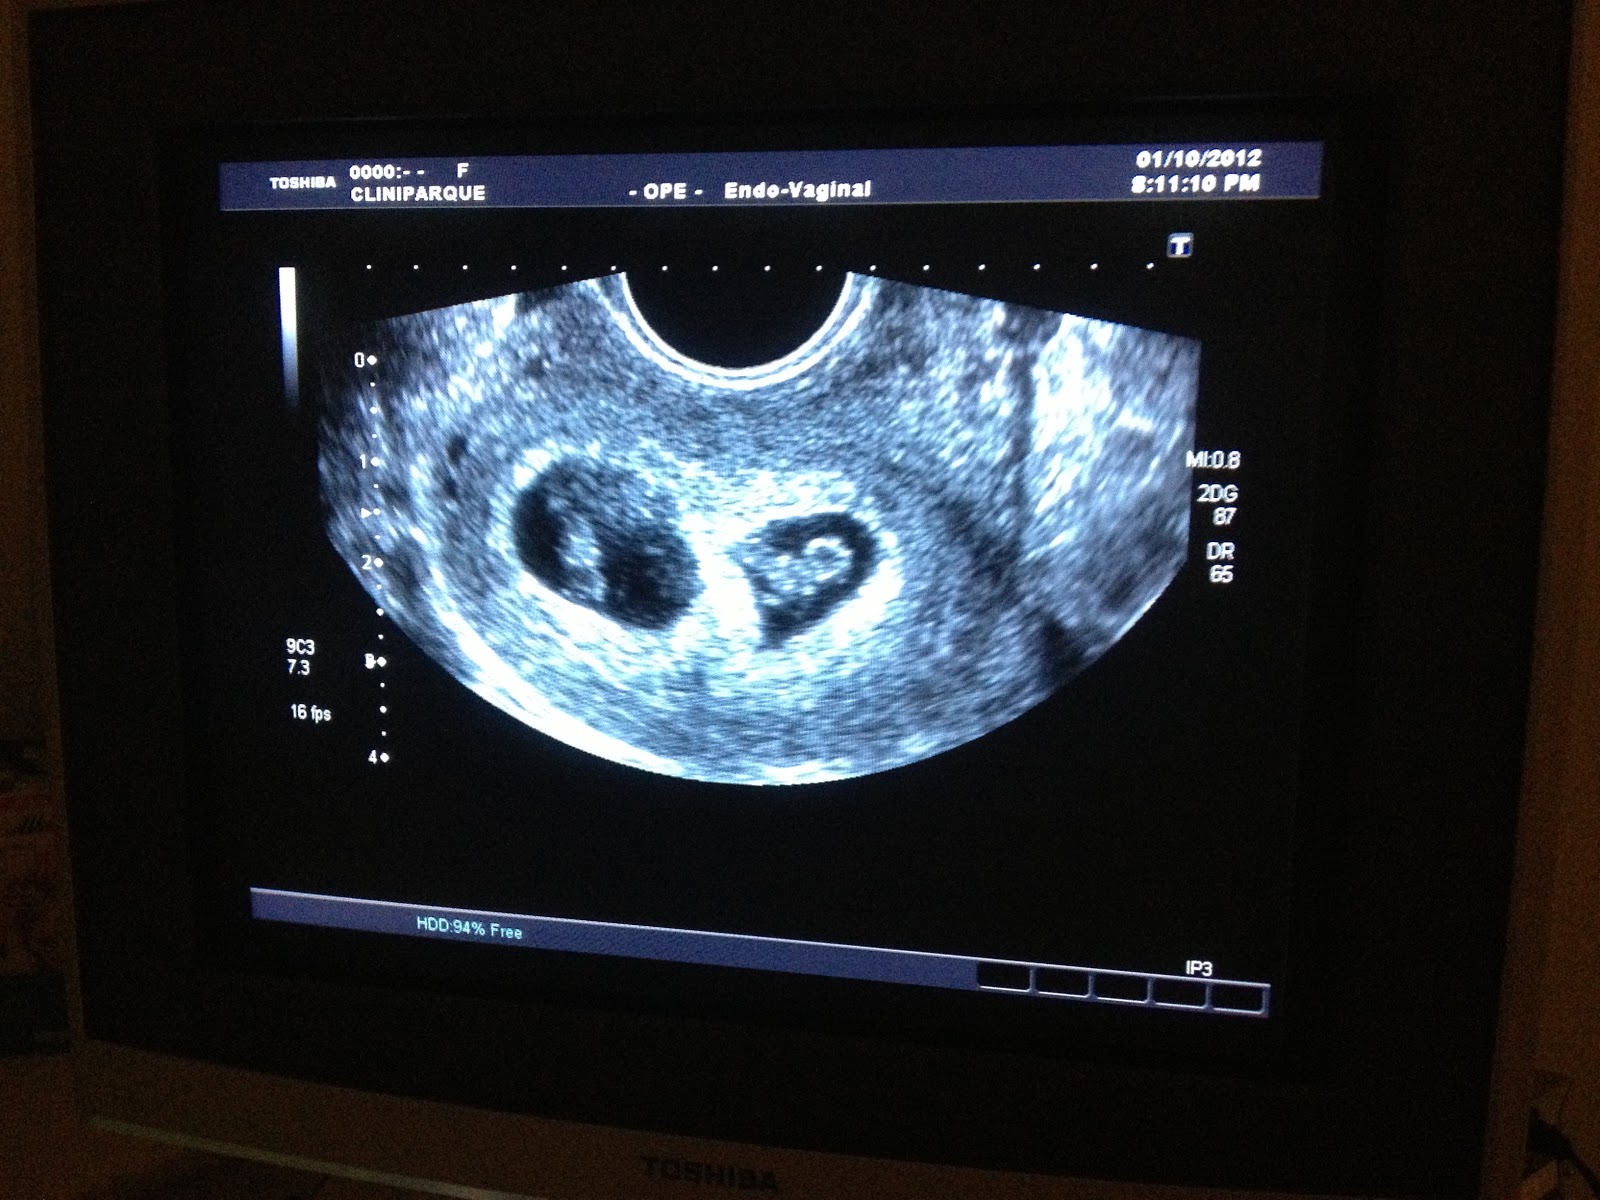

Gravidez De Gemeos Semana A Semana, GRAVIDEZ DE GÊMEOS!, 27.42 MB, 19:58, 196,217, Mãe-Estar, 2019-03-13T20:53:28.000000Z, 3, Twin Parenting: Week by Week Twin Belly, twin-mommy-blog.blogspot.com, 1096 x 575, jpeg, WebGravidez gemelar semana a semana. Semana 9 Nesta semana, os dois embriões já são detectados por ultrassom. Será neste primeiro ultrassom quando você ficará sabendo. WebNo final da semana 24ª semana de gravidez, o feto pesa cerca de 630 gramas. Um feto que nasça neste período pode tentar respirar, mas na maior parte dos casos não sobrevive., 20, gravidez-de-gemeos-semana-a-semana, Informação e Entretenimento WebGravidez gemelar semana a semana. Semana 9 Nesta semana, os dois embriões já são detectados por ultrassom. Será neste primeiro ultrassom quando você ficará sabendo. WebNo final da semana 24ª semana de gravidez, o feto pesa cerca de 630 gramas. Um feto que nasça neste período pode tentar respirar, mas na maior parte dos casos não sobrevive.

WebGravidez: 17° Semana de Gravidez; Namoro. Namoro: 0 a 12 meses; Namoro: 1 a 3 anos; Namoro: 3 a 6 anos + Recente + Destaques. 3 anos e 3 meses de namoro; 3 anos e 2. WebA gestação gemelar semana a semana, é uma forma de você acompanhar o desenvolvimento dos seus bebês. Como você já deve saber, na. Webàs 12 semanas os bebés são do tamanho de uma ameixa e medem cerca de 5cm de comprimento e 15 gramas de peso cada. Dentro de quatro semanas seus bebês. Web9 meses - 36 a 42 semanas de gestação. O 9º mês de gravidez, corresponde às semanas 36 a 40 semanas, mas pode se estender até às 42 semanas. Mudanças no bebê: nesta. WebGravidez semana a semana de gemeos fotos East Sussex curso de cupcake sp Columbus, Charleston, State of South Carolina, apresentador do globo. WebConfira como gêmeos crescem dentro da barriga. A única forma certa de confirmar uma gravidez múltipla é através de um exame de ultrassom. É até possível visualizar gêmeos. WebDurante a sexta semana de gravidez o embrião mede cerca de 4 mm desde a cabeça até às nádegas e o seu coração começa a dar os primeiros batimentos. O tubo neural, que. WebEntre os riscos que uma gravidez gemelar pode apresentar, além da alta taxa de prematuridade nos bebês são: hipertensão, diabete, taquicardia e problemas renais..